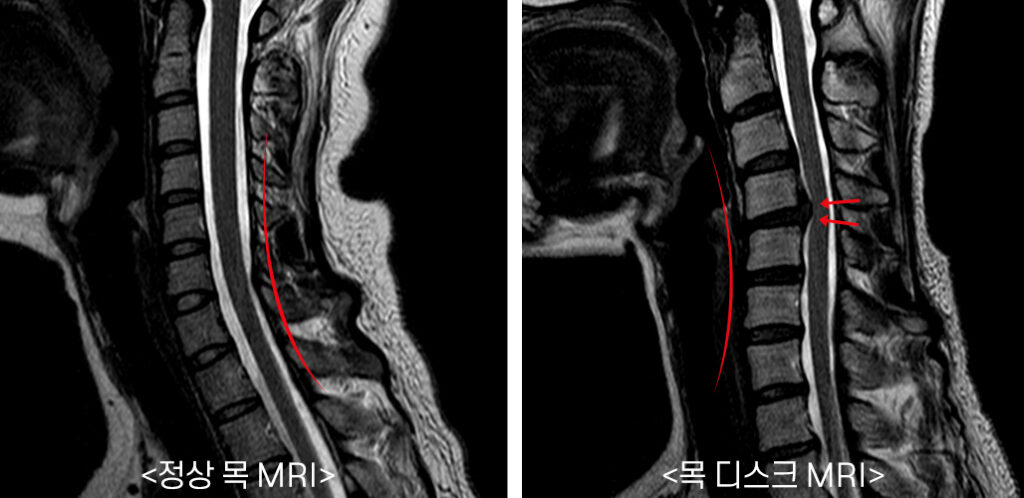

목 디스크는 목의 디스크(경추 디스크)에서 출현하는 질환으로, 경추 디스크 사이의 연골판이 터져 디스크 내부 물질이 경추 신경을 자극해 통증이나 저림증 등의 증상을 유발 해요. 목 디스크는 일상생활에서의 안 좋은 자세나 많은 운동, 부상 등이 이유가 되는 것이 될 수 있기도하고, 시간이 지날수록 발생 확률이 높아져요. 목 디스크의 증상으로는 목 부위의 통증, 팔의 저림, 근육 약화 등이 있으며, 증상이 난폭한 경우 수술 등의 치료가 필요할 수 있어요. 그리하나 대개의 경우 치료 없이도 시간이 지나면 증상이 호전되는 경우가 대부분입니다.

추간판의 수핵이 빠지거나 퇴행성 경추증 및 경추관협착증 등으로 척수가 압박되면 대다수 팔에 힘이 빠지는 것을 느끼게 돼요. 척수가 눌리는 정도이기 때문에 한쪽 팔만 마비될 수 있고요. 하지마는 양팔의 감각이 둔해지고 눈을 감고도 어지럽기 때문에 이러한 목 디스크 증상이 나타나면 무척 위험한 상태가 되기 때문에 빨리 치료가 필요해요.

척수라는 중추 신경은 목뼈를 통과해 목 아래 감각과 운동 신경에 영향을 끼치기 때문에 목 디스크 증상들이 나타나면 신속하고 빠른 대처가 필요해요. 목디스크 치료형식으로 주로 초기 스탭에는 물리치료나 약물을 통해 대개의 환자들이 호전돼요. 그렇지 않다고 하면 신경 성형술과 차단술이라고 부르는 뼈주사 목디스크 치료방법을 이용하는데, 이 치료방법은 통증이 있는 신경 부위에 약물을 삽입하는 것입니다.